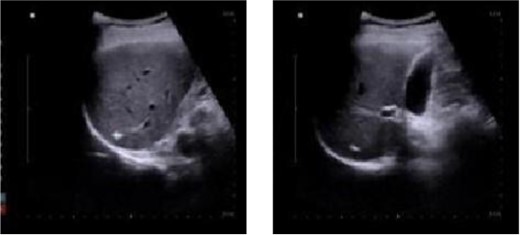

One week after discharge, the patient underwent a follow-up examination at the outpatient department, which revealed significant healing of the surgical wound. The patient reported a normal appetite, absence of fever, and no abdominal pain or discomfort. Additionally, 1 month post-operation, a review of abdominal color ultrasound demonstrated the absence of inflammatory lesions in the liver (Fig. 3).

Abdominal color ultrasound findings on the 30th day after surgery.